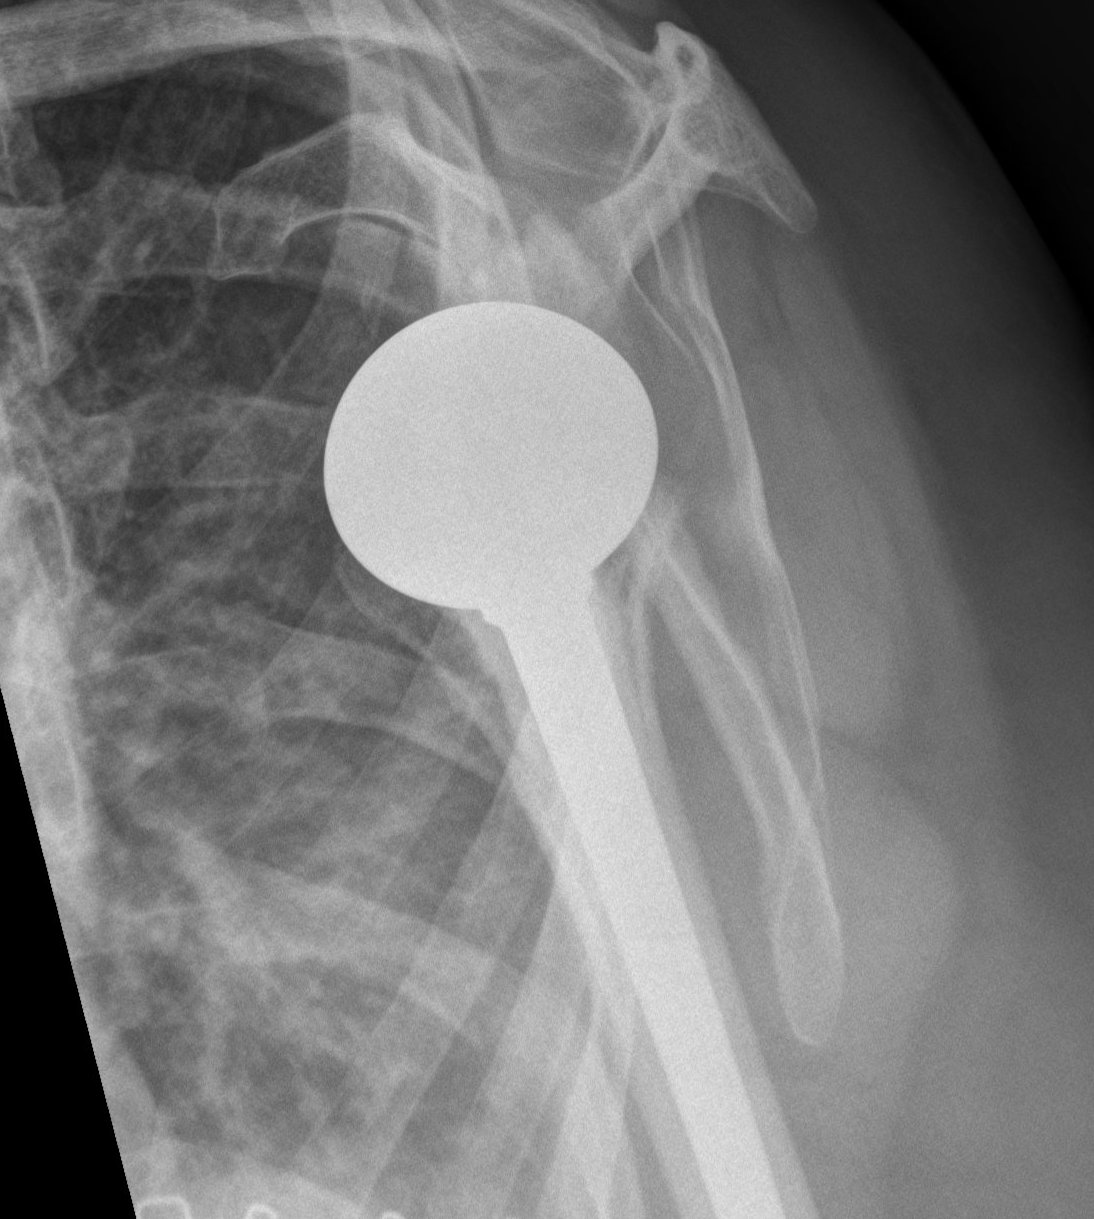

Aseptic loosening

TSR Loose glenoidaTSA loose glenoid

Glenoid Component LooseningHumeral resurface loose

Incidence

Schoch et al. JSES 2019

- 492 aTSA at 5 year follow up

- 308 (63%) had no radiolucent lines

- 184 (37%) had peri-glenoid lucency

- those with glenoid lucency had decreased ROM and patient-reported outcomes

Melis et al. JSES 2012

- 37 patients with loose glenoids revised to rTSA

- all had glenoid bone deficiency

- 29/37 required bone grafting

- 8/37 (21%) required reoperation - glenoid loose (3) / anterior instability (3) / humeral subsidence (2)